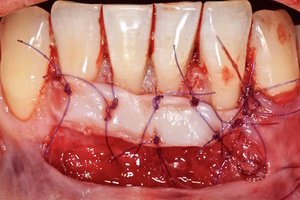

Протокол хирургической операции:

1. Измерены глубины рецессий (ГР), эти замеры отложены от вершин межзубных сосочков в апикальном направлении в сторону зенита рецессии.

2. Дизайн разрезов соответствует методике Zucchelli G. коронально-ротированного смещения (2000).

3. Мобилизация слизисто-надкостничного лоскута, деэпителизация анатомических сосочков, обработка поверхности корней зубов.

4. Фиксация пластического материала ТМО (dura mater) к поверхности корней зубов в области зоны создания необходимого объема прикрепленной десны.

5. Закрытие пластического материала слизисто-надкостничным лоскутом со смещением в корональном направлении, и фиксация слизисто-надкостничного лоскута швами; дополнительная фиксация зоны перемещенных и в будущем созданных мягких тканей десны в зоне рецессии десны для стабилизации результата операции.

6. Обработка поверхностей корней зубов проводилась аналогично (см. выше).